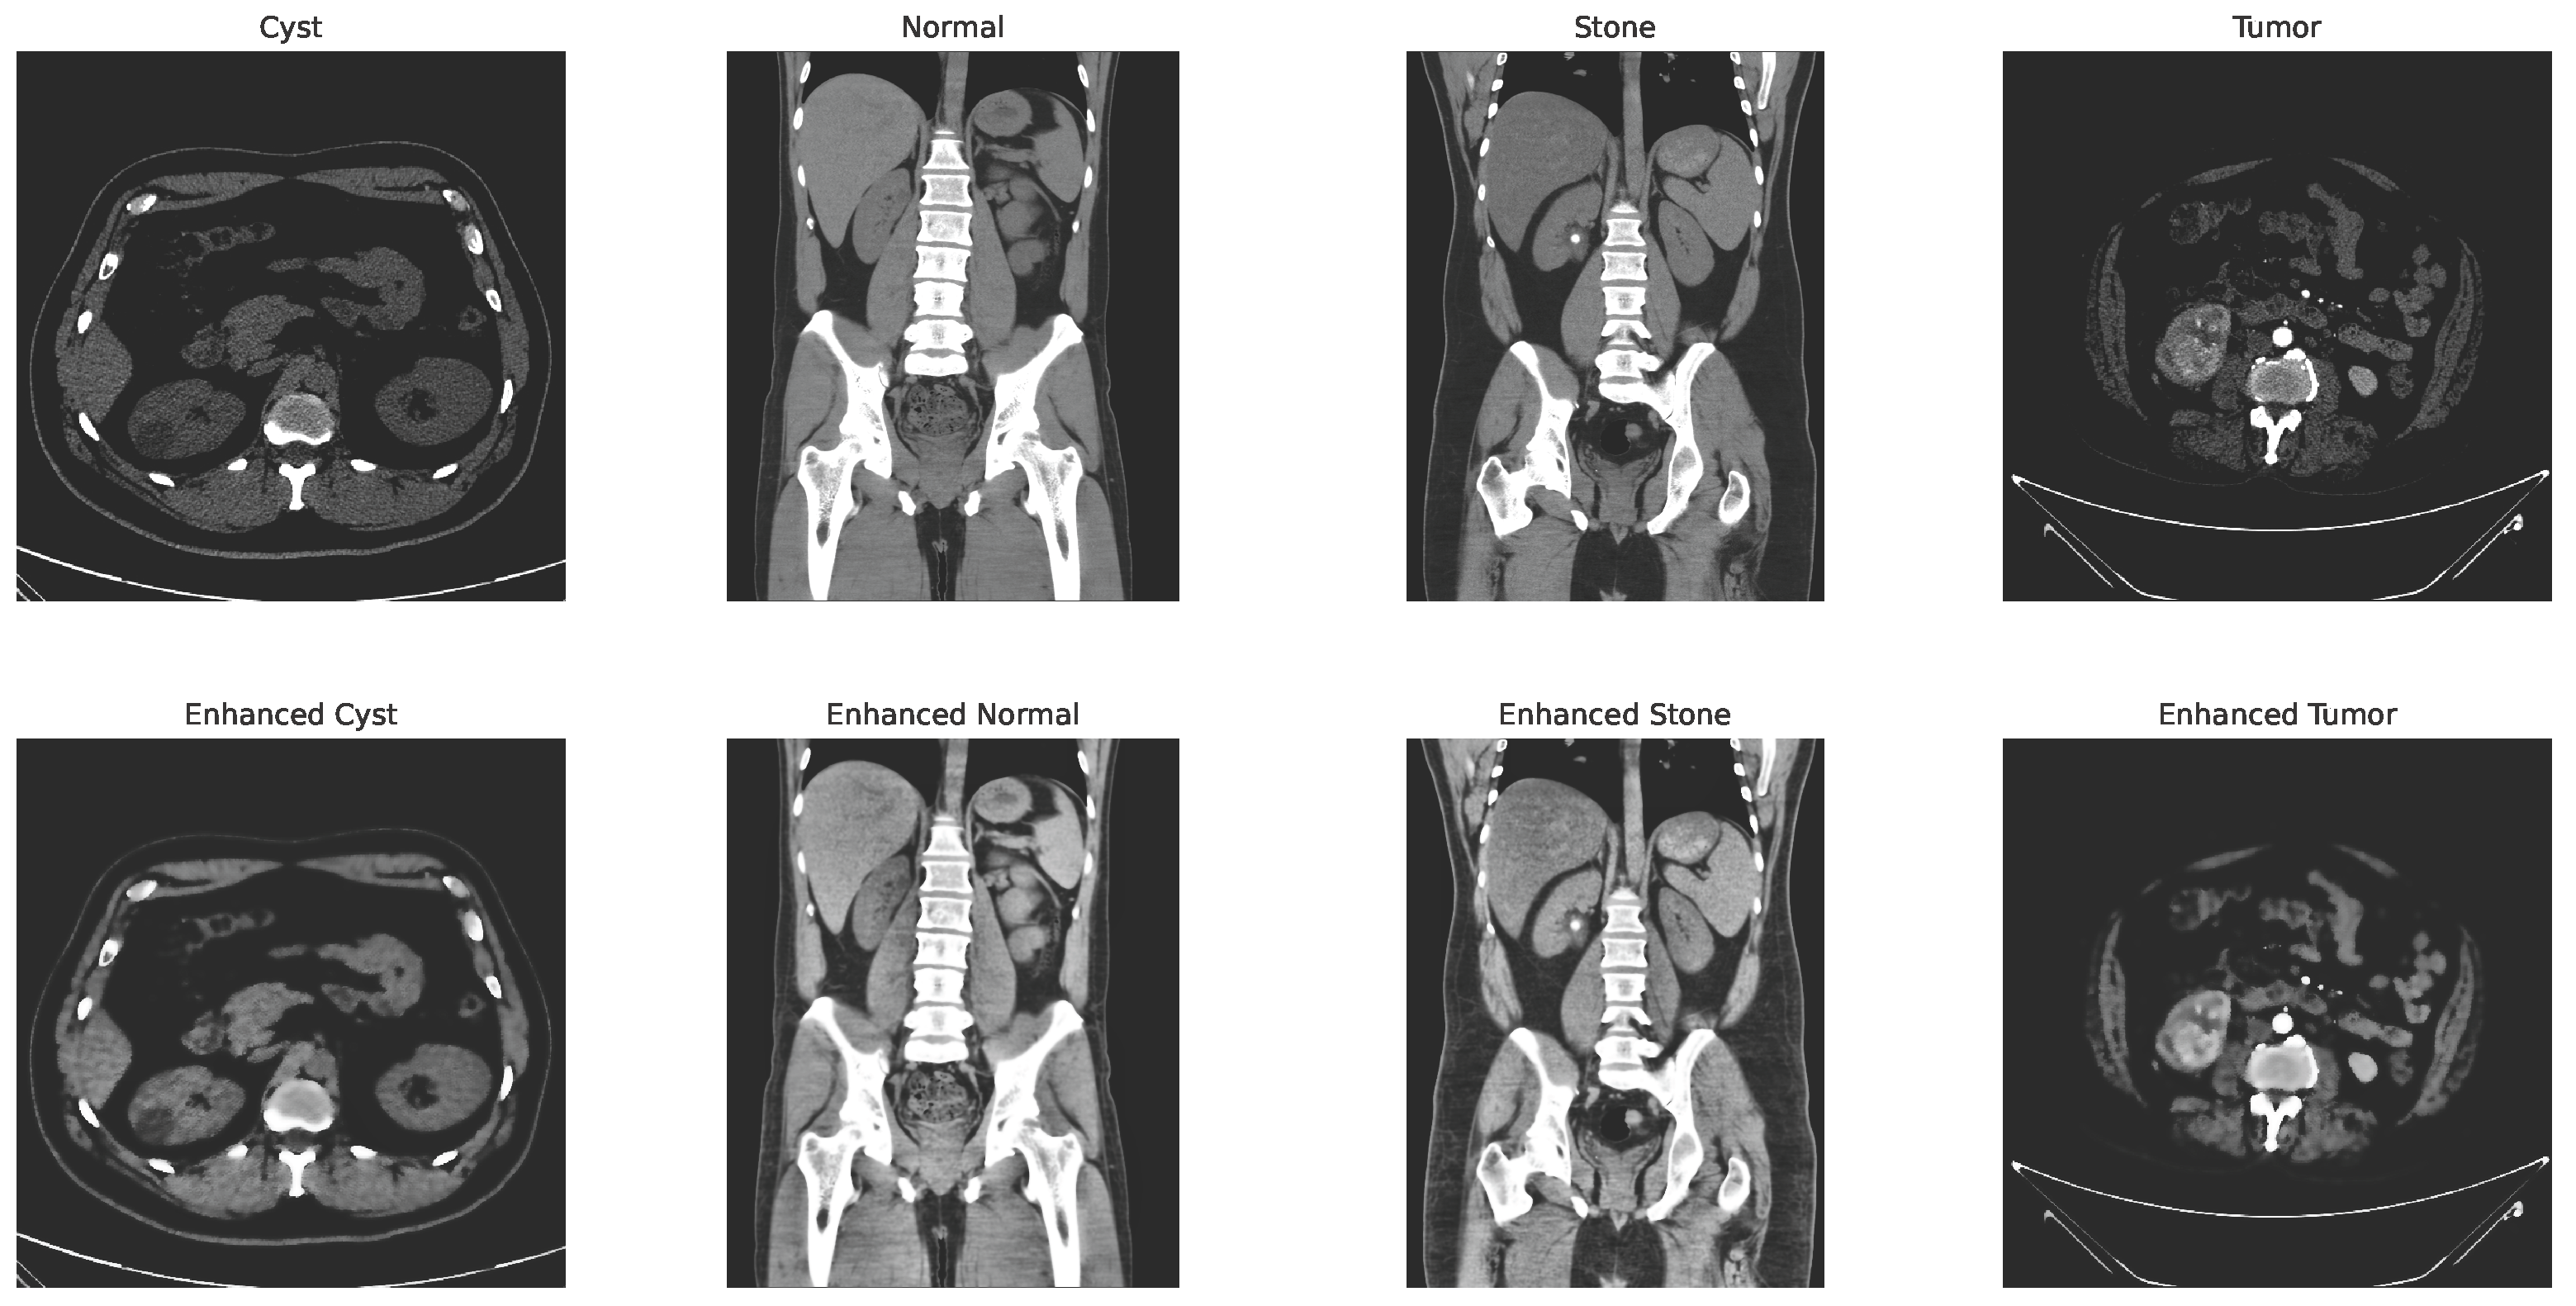

with and representing the spatial and range kernel functions, denoting the neighborhood, and acting as a normalization factor. Figure 4 shows the changes in the image after applying the CLAHE and bilateral filtering.

Figure 4.

CLAHE + bilateral filter enhanced image.

To further augment the dataset and aid in generalization, transformation techniques such as rotation, flipping, and zooming were applied [46]. All enhanced images were then resized to pixels, converted to RGB format, and normalized using ImageNet’s mean and standard deviation , expressed as Equation (4):